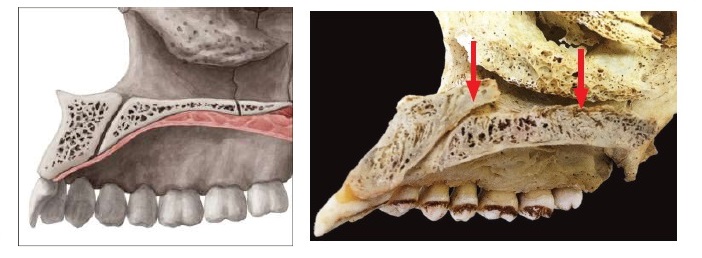

The below picture shows the division of the three parts of the palate: the anterior segment before the incisive foramen; the middle segment from the incisive foramen to the transverse palatine suture; the posterior segment, after the suture to the palatal bone.

Different studies have analyzed the bone density of the palate, showing that:

- The midpalatal area close to the midpalatal suture has the thickest bone.

- The further posterior part of the palate presents lower bone density (as can be also seen from the picture above).

Thicker bone represents a better anchorage for the screws, reducing the risk of screw dragging. For this reason, doctors prefer to place the appliance more anteriorly in the midpalatal segment to reduce the risks of failure. The anterior segment also presents less resistance from other surrounding structures, thus more anteriorly the appliance is placed, more expansion can be achieved in the anterior segment. However, the posterior part has a higher resistance, because it is more engaged with other surrounding structures (for example think about the engagement of the zygomatic area, palatine and sphenoid bone that happens more posteriorly). This can thus result in a more conical/triangular or V-shaped expansion, which implies less benefits for the expansion of the airways (less nasal volume increase) and less midface changes.

An appliance placed more posteriorly increases the chances of a more parallel expansion of the midpalatal suture, thus resulting in more benefits for the nasal volume and midface. However, this presents also higher risks of failure since the resistance in that area of the palate is higher and the bone is less dense. The forces generated by the appliance have to overcome the resistance located in the midface such as the pyriform aperture pillars, zygomatic buttresses, pterygoid junctions, midpalatal suture, etc.